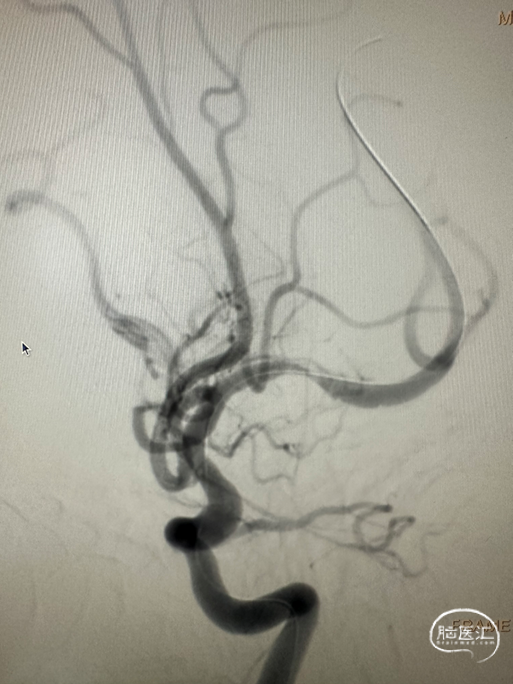

4.0*23mm 自膨式闭环支架沿21系列 Fastunnel®输送型球囊扩张导管输送到位造影。

支架释放后造影。

患者麻醉复苏后无神经功能障碍。患者术后标准正侧位造影。